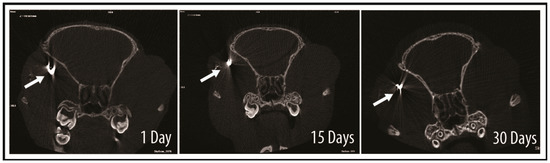

2.4. Tracking of GNP-Labelled MSCs by Micro-CT